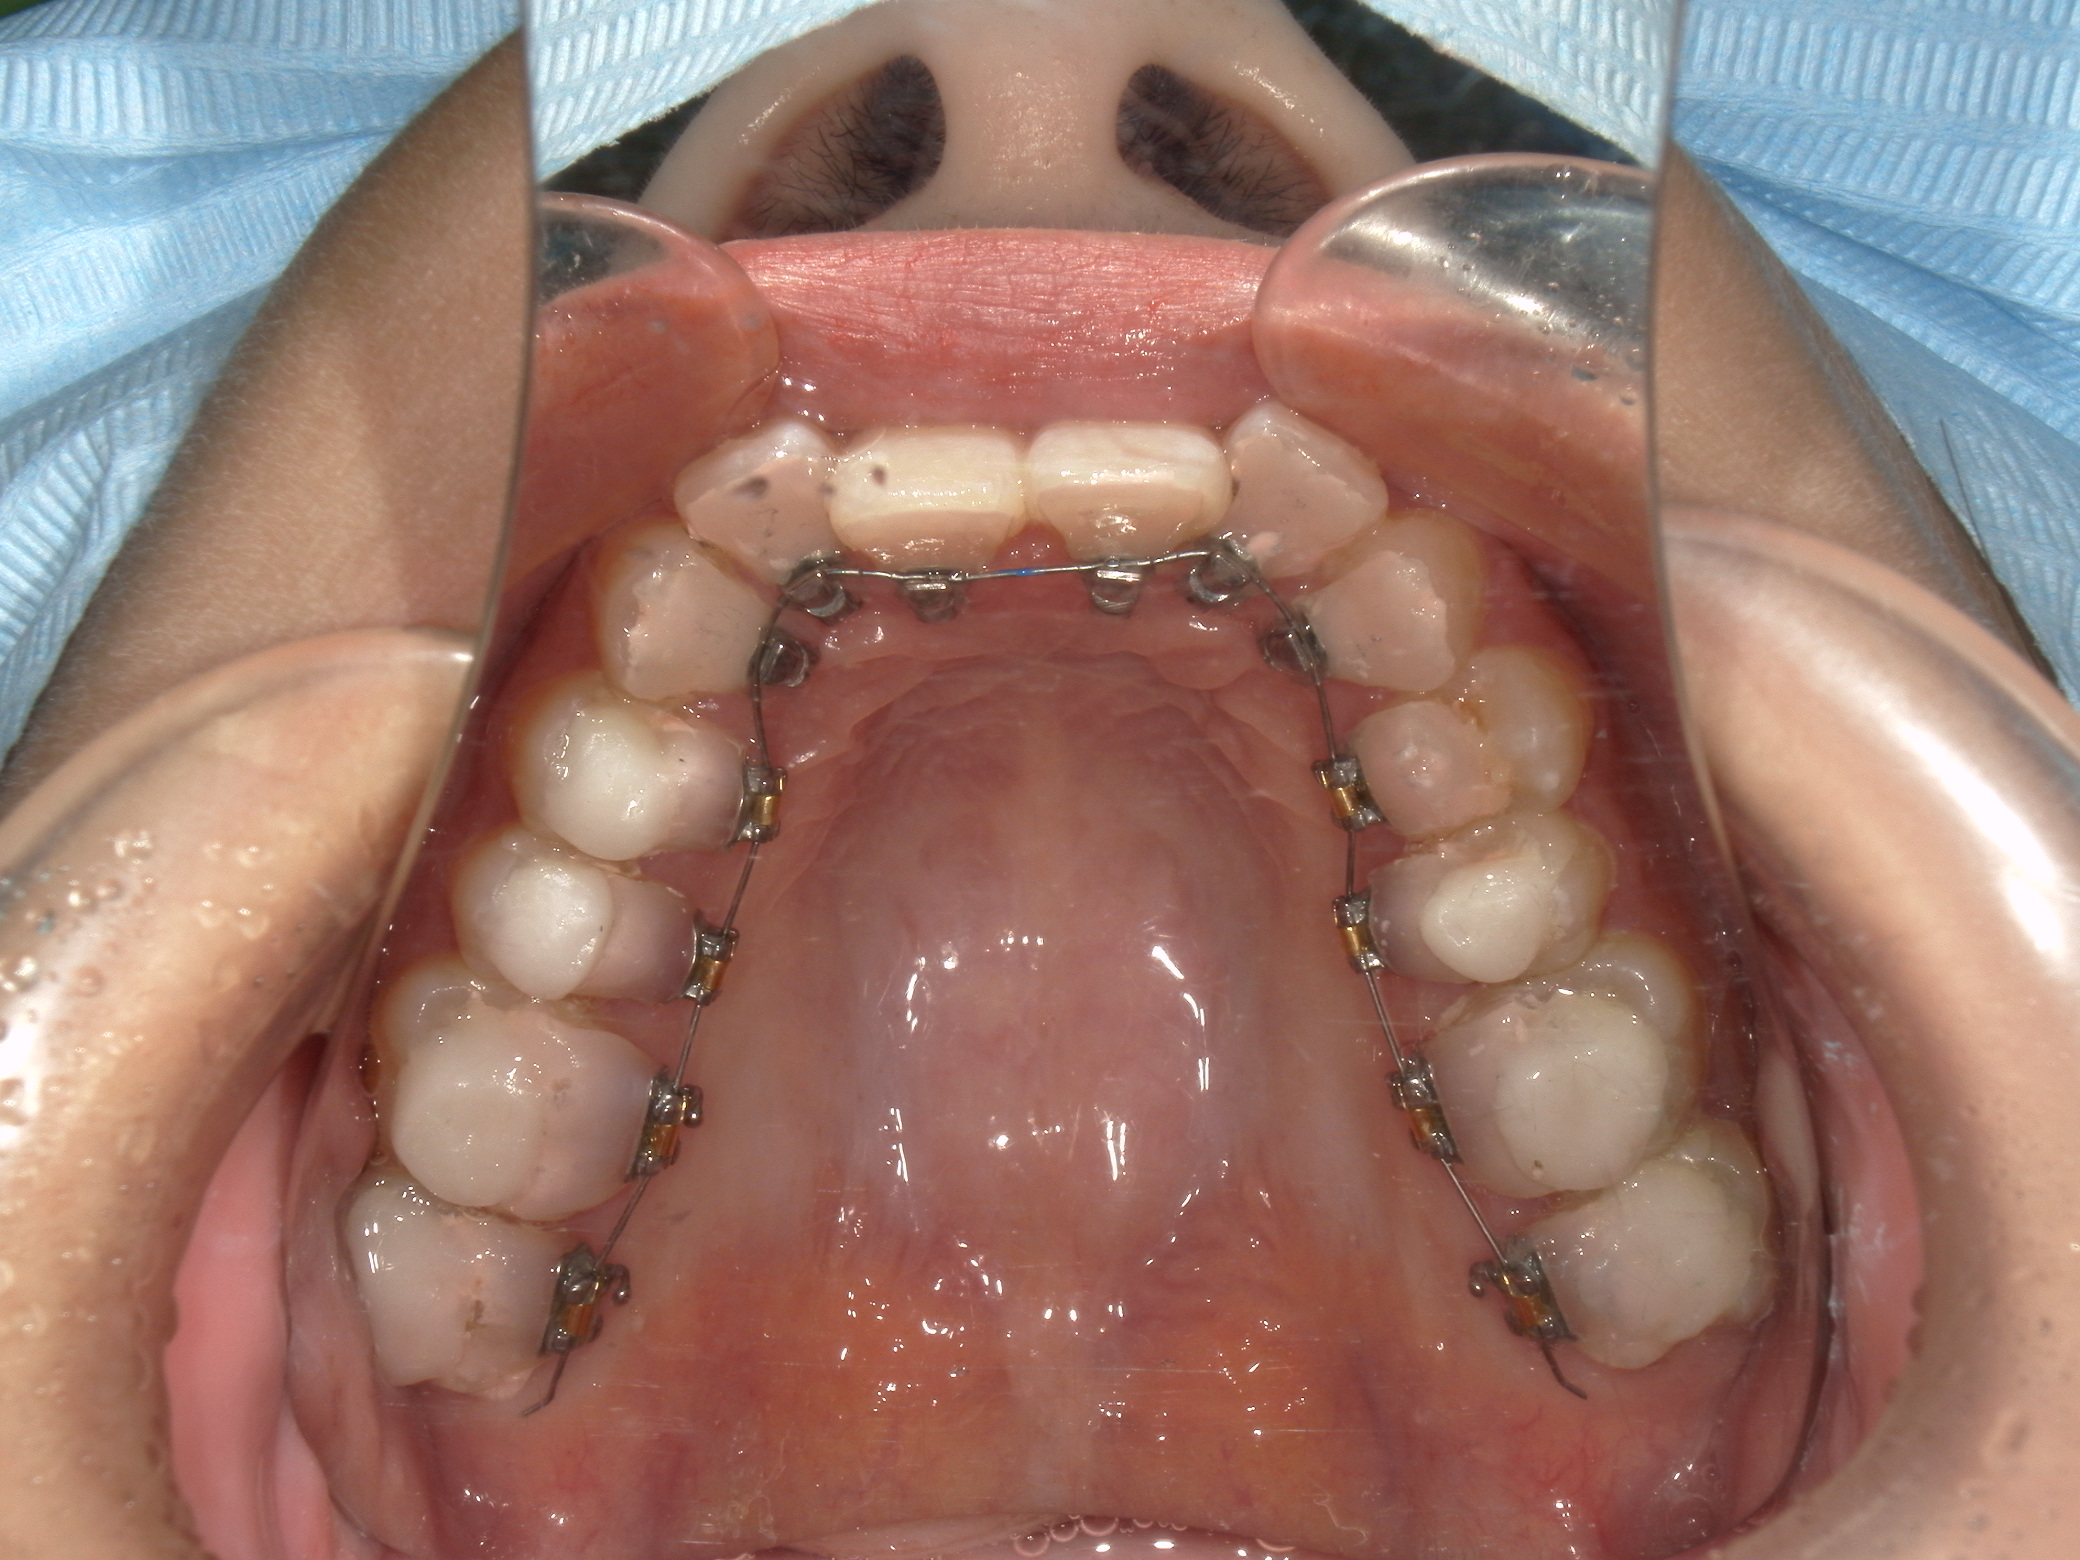

裏側矯正11

ご相談内容・お悩み

歯並びのガタガタ

かみ合わせが深い

治療内容

上下顎に叢生(歯並びのガタガタ) と過蓋咬合を認める。

Ⅱ級2類不正咬合は下顎が小さく顔貌のバランスが良いため、抜歯を選択する場合は叢生量から検討する。本症例は非抜歯による舌側矯正治療を選択した。

本来過蓋咬合は舌側矯正には不向きだが、当院のオリジナルブラケットであるFLBシステムにより良好な結果が得られた。